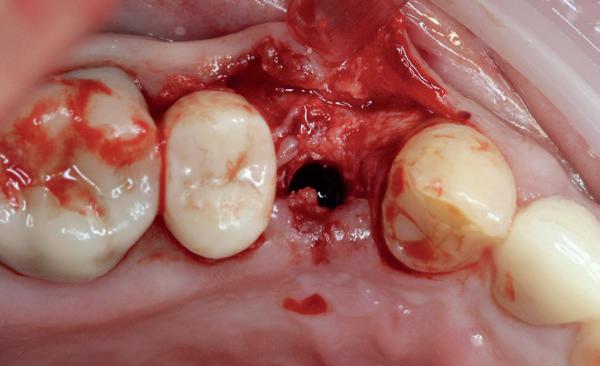

2. Decapiteren van het element en splitsen van de wortels.

3. Verwijderen van de radices.

4. Curettage en spoelen met een zoutoplossing.

5. Het ridge preservation protocol waarbij we proberen zoveel moge-

lijk bot te behouden met behulp van een xenograft.

tijd probeerde de buccale botlamel intact te houden. Dit is cruciaal voor latere botbehoud en implantaatplaatsing. Na curettage en spoelen van de alveole beoordeelde ik de situatie opnieuw: de botcondities leken gunstig voor een immediaat implantaat.